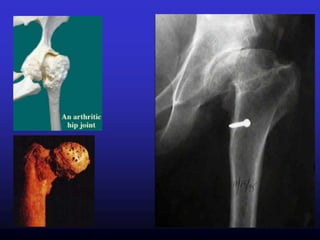

Sinais radiográficos clássicos de

artrose:

• Estreitamento do espaço articular

(porção infero-interna)

• Esclerose subcondral (cartilagem

articular fina e estreita)

• Presença de osteófitos marginais

(Δ ausência de carga)

• Aparecimento de cistos ( Δ

estresse mecânico)

Sinais radiográficos clássicosde artrose: • Estreitamento do espaço articular (porção infero-interna) • Esclerose subcondral (cartilagem articular fina e estreita) • Presença de osteófitos marginais (Δ ausência de carga) • Aparecimento de cistos ( Δ estresse mecânico)